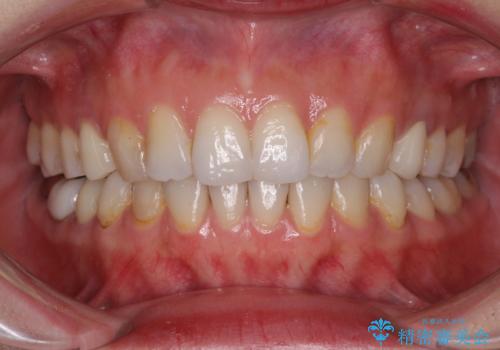

- 失活により変色した歯と不揃いな口元を気にして来院された患者様です。

口元をインビザラインにより歯列を整え、その後に失活している奥歯をオールセラミッククラウンにて補綴治療することとしました。

長時間のマウスピース装着と、患者様自身でのゴムかけに協力いただき、自然な口元に仕上げることができました。

気になっていた変色した歯もオールセラミッククラウンで本物の歯のようになり、患者様には大変満足していただきました。